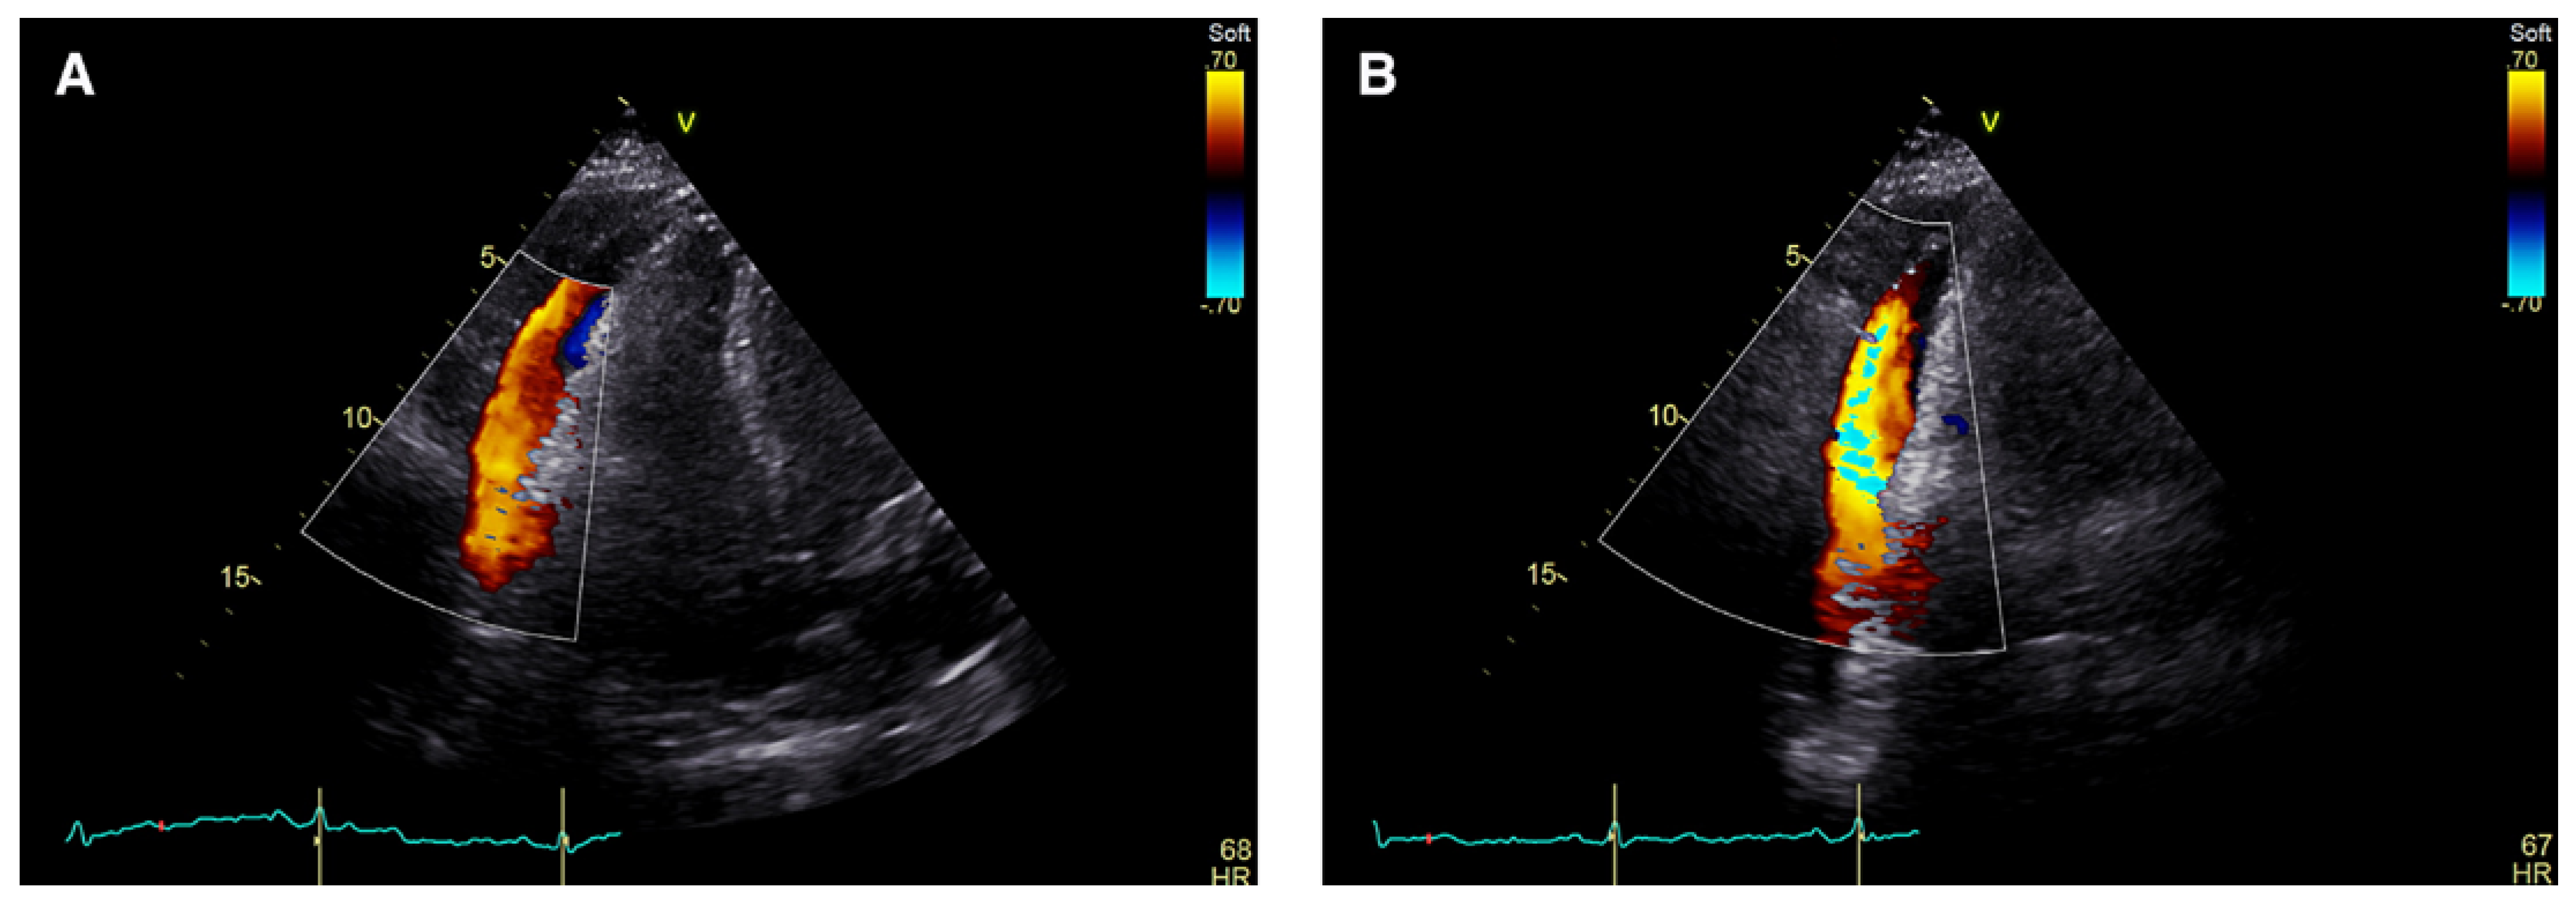

Intrapericardial Doppler Flow Signals in a Patient with Pericardial Effusion

Case Description